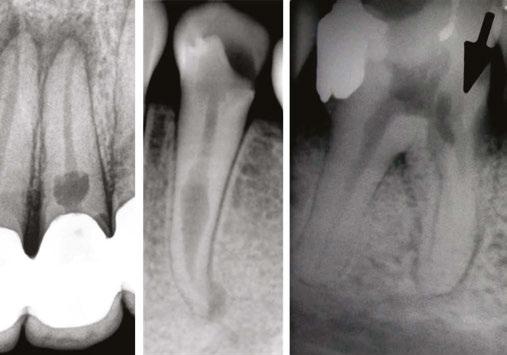

Judy McIntyre, DMD, MS Figure 1: Acutely curved and calcified buccal canal right under upper left premolar crown margin; valuable information for access and management. No. 9 also has a PARL, which was only incidentally captured Figure 2: Large PARL with destruction of the maxillary sinus floor and sinusitis as a result

About 10 years after completing residency, I opened my own practice and invested in a DEXIS CBCT. Initially, I only used it for apicoectomies and retreatments. In time, I began to realize how helpful it was for all my cases. With the 3D-scan information (Figure 1), I could have saved myself some humbling experiences and surprises. Endodontists hate surprises, and we really hate failures! Once I started using my CBCT more frequently, I was able to appreciate things that would have otherwise been intra-op surprises and plan for them prior to starting the procedure. The 3D data allows me to properly assess prognosis, determine the best course of treatment, and plan that treatment with a level of precision that is impossible otherwise.

Figure 3: Second maxillary molar with external root resorption (ERR) with incidentally captured ERR on the lower mandibular first molar as well. When there is one tooth with resorption, be suspicious of other teeth with resorption, especially on younger patients Figure 6: No PARL on PA film. Clear PARL on scan taken with medicament Figures 4 and 5: 4. Mandibular molar with a J-shaped lesion due to endo — not a vertical root fracture. Path of least resistance happens to be through a distal perio pocket, but this is an endo-perio lesion and not a VRF. Incidentally, a mucous retention cyst was captured in the sinus. 5. Healing after bridge removal and retreatment

a realistic prognosis. Unfortunately, not all teeth can be saved. Some are not candidates for retreatment (Figure 11). Without a CBCT scan, it would be easy to attempt these retreatments only to discover the true problem mid-treatment, or worse — to think I had caused one (Figures 10 and 11). This added information not only helps the practitioner, but also provides patients a higher level of confidence and trust in you.

With retreatments, maybe the root canal looks completely fine on a PA or panoramic x-ray, but the patient says that it just doesn’t feel right. A cone beam can often reveal the cause of the patient’s discomfort. This could be that the tooth was perforated, cracked or has an unfilled canal, and the patient is totally justified in feeling like something’s wrong. Or sometimes the scan will show that there is another issue on an adjacent tooth or in the patient’s sinuses (causing their discomfort). When patients sense a problem but are told that there is not one (usually based on 2D radiographs), that’s not a great feeling. Being able to show the patient the CBCT scan and say, “You were right, and here’s the issue,” improves the patient experience.